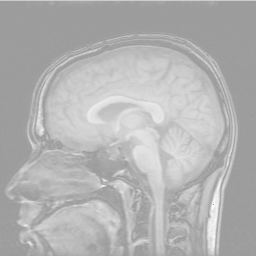

Find the corpus callosum

Applications in biological imaging.